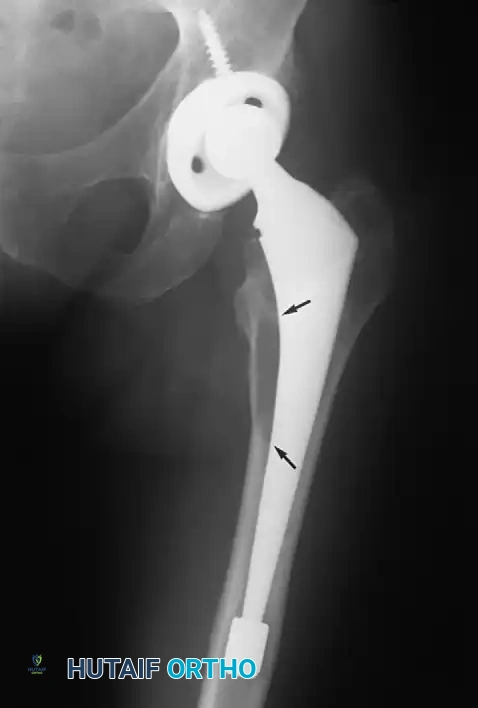

Associated Surgical & Radiographic Imaging